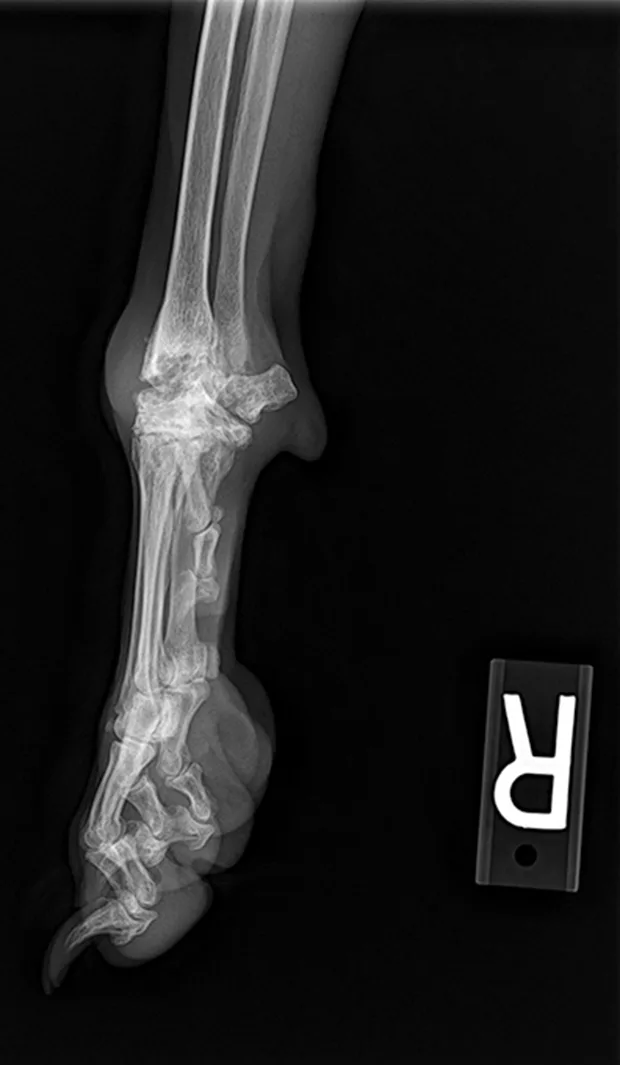

Tarsus

Lateral and craniocaudal views of hock. Insert the needle just distal to the lateral malleolus at a 30°–45° angle in a craniomedial direction.